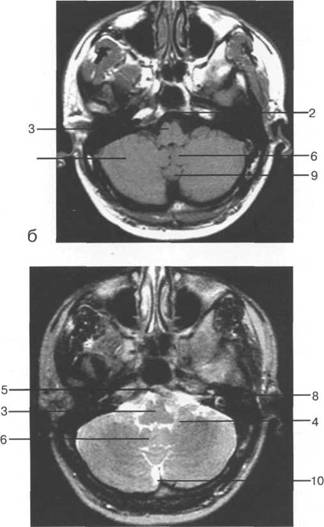

Задняя череп 13513u2010n 85;ая ямка представляет собой часть основания череп 13513u2010n 72;, ограниченную централь

Следует отметить, что в настоящее время оптимальным методом исследования структур задней череп 13513u2010n 85;ой ямки является МРТ, которая, в отличие от КТ, лишена артефактов от кост

Мозжечок заполняет практически весь объем задней череп 13513u2010n 85;ой ямки. Его поперечный раз

Следует остановиться на анатомии подпаутинных пространств задней череп 13513u2010n 85;ой ямки IV 20 мм. Между основанием череп 13513u2010n 72; и нижней поверхностью мозга от большого затылочного отверстия вдоль ската и спинки турецкого седла простирается задняя базальная цистерна. В зави IV